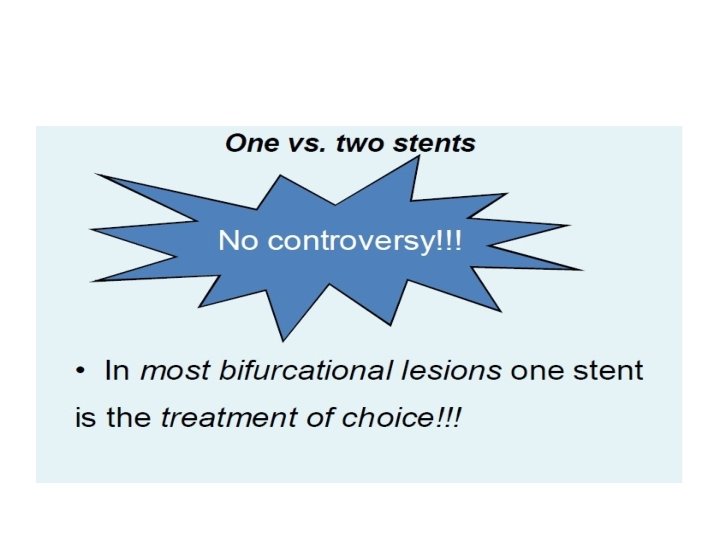

One vs two stents • • • Important trials NORDIC 2 BBC CACTUS

When to use elective two stents?

1. Nordic I: provisional T stenting as good as systematic side branch stenting 2. Nordic II: Culotte better than Crush 3. Cactus: provisional T stenting not worse than crush 4. BBC ONE: step wise approach with provisional T stenting better than initial complex procedures 5. Bad Krozingen: no difference provisional vs systematic T 6. Double Kiss Crush Study: DK Crush better than conv. crush Steigen Circulation 2006; 114: 1955; Erglis TCT 2008; Hildick-Smith TCT 200 Ferenc EHJ 2009; Chen JInterv Cardiol 2009; 22: 121 -27